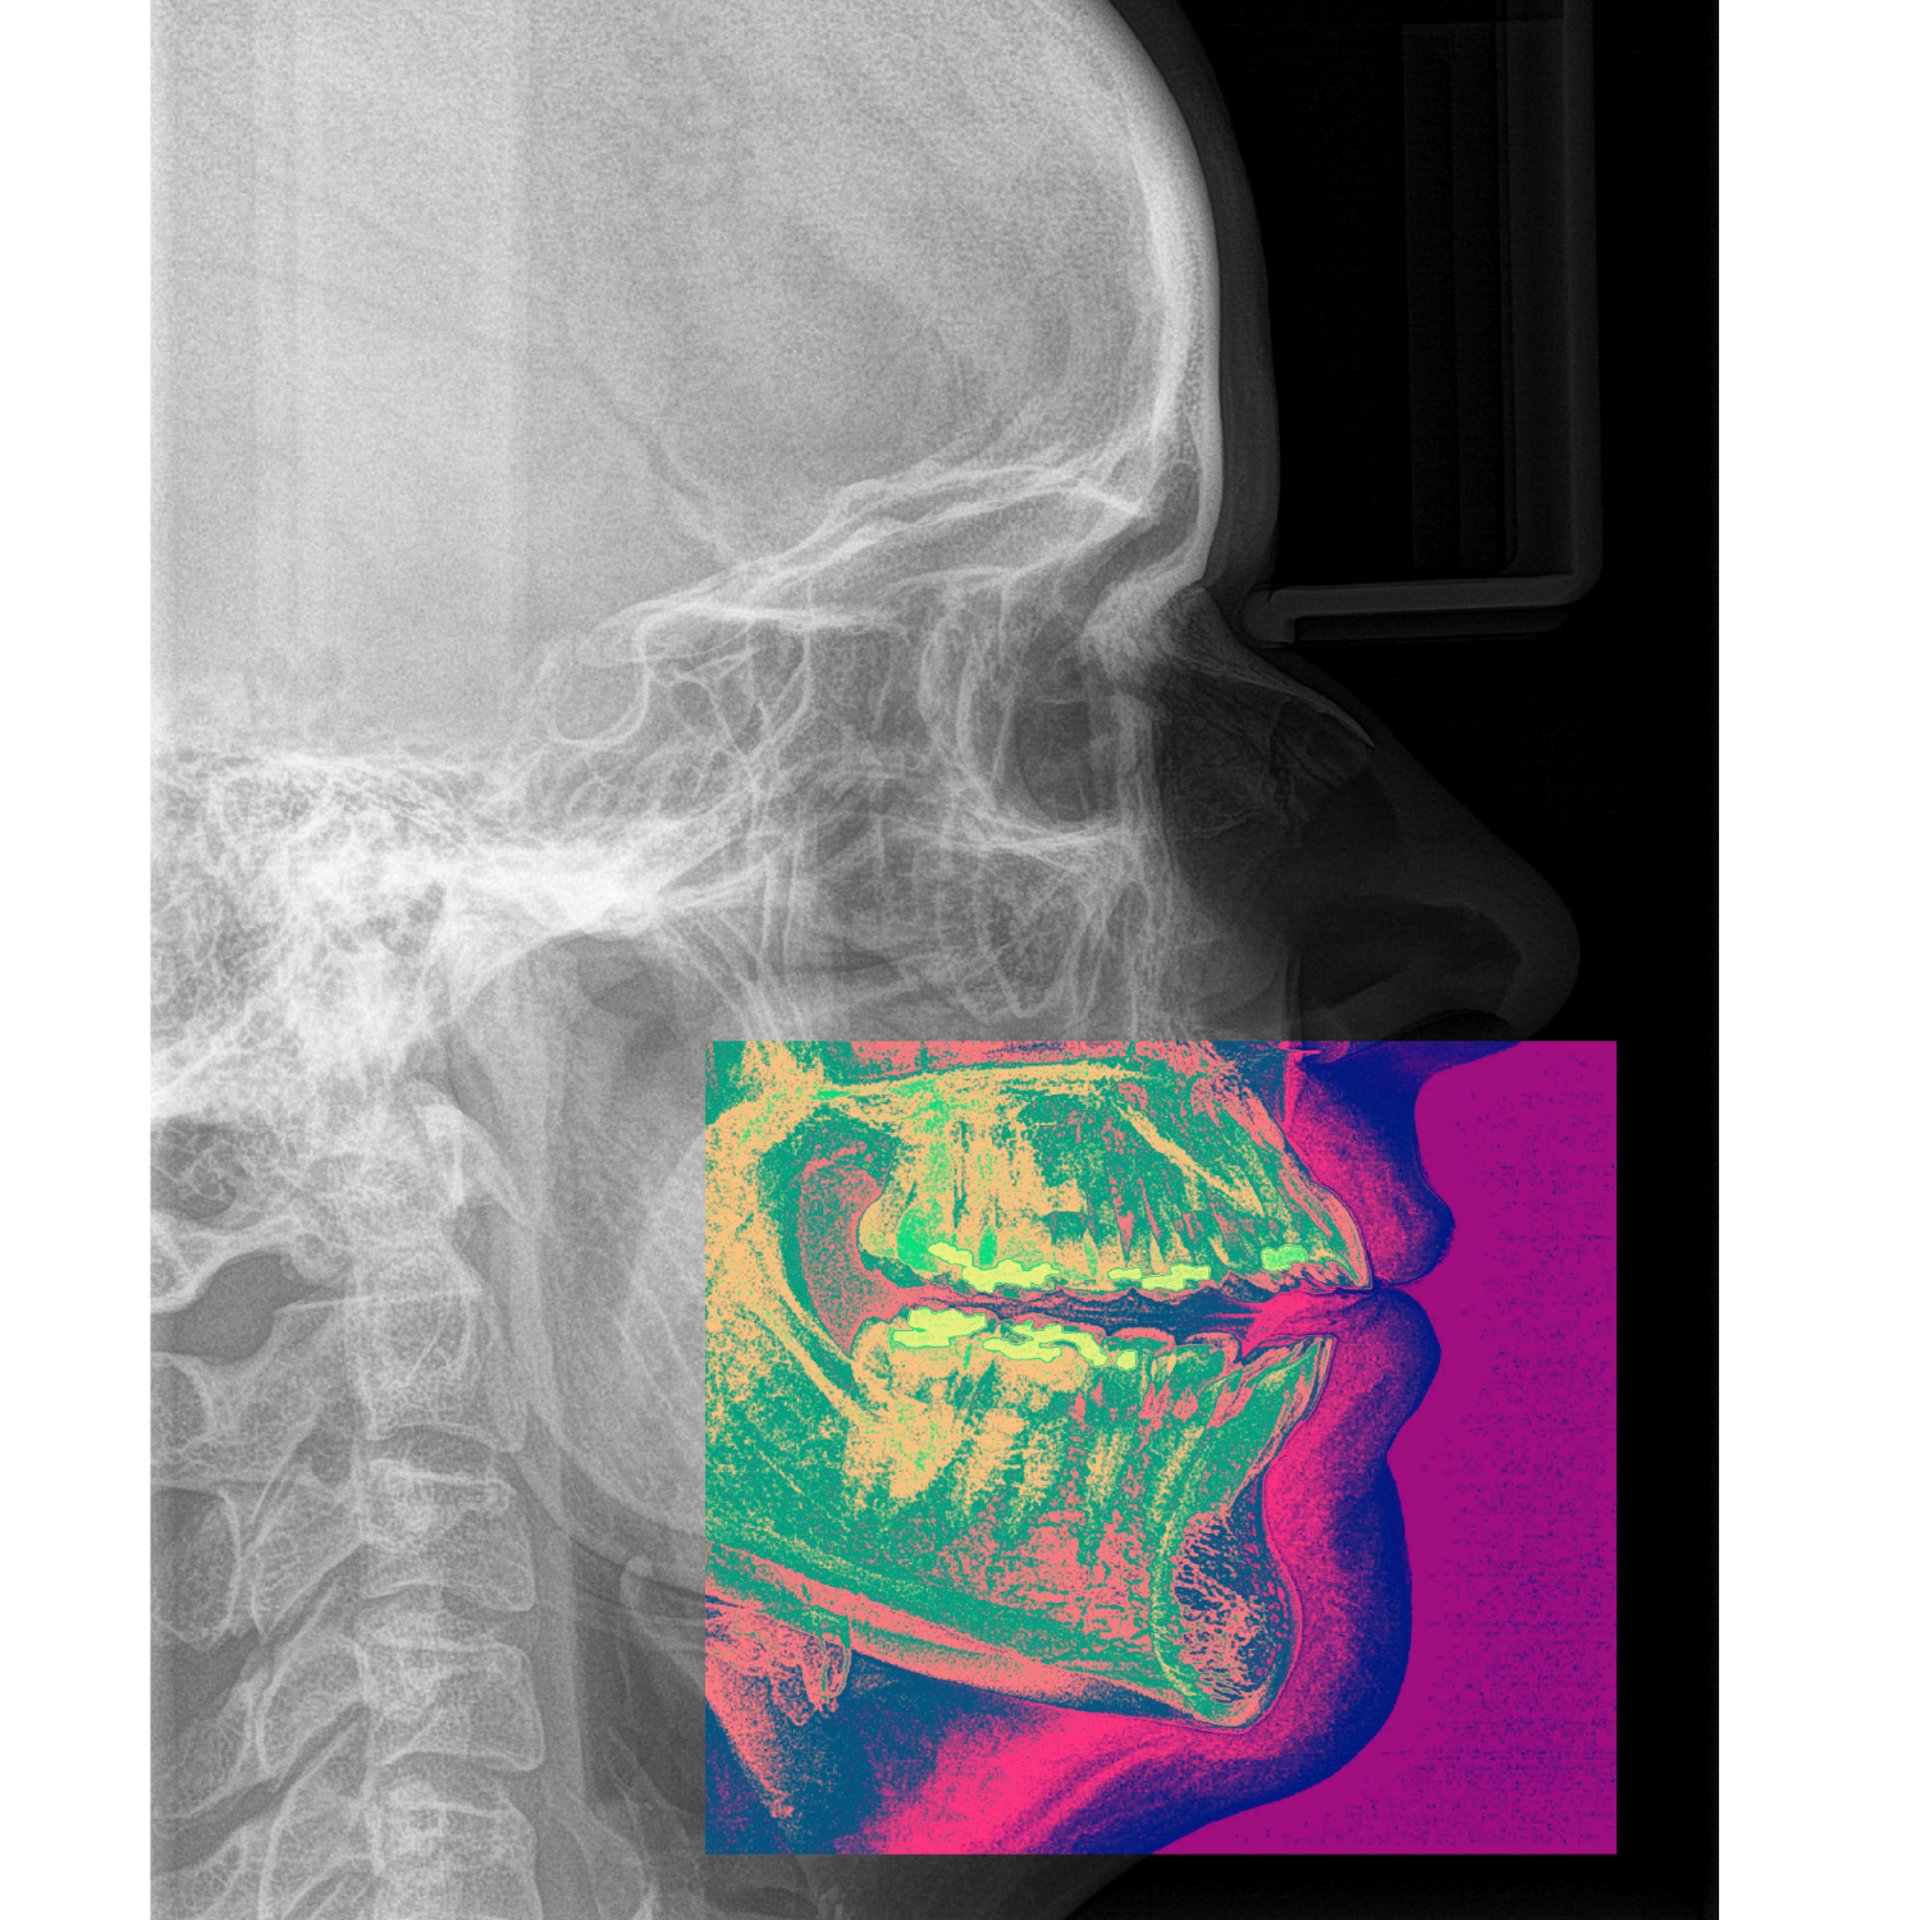

A DVR é a posição em que a mandíbula repousa naturalmente, em equilíbrio neuromuscular, quando os músculos elevadores e depressores estão em tônus mínimo. Não é força, não é contato, não é intercuspidação. É o espaço fisiológico — sutil, individual, dinâmico — que separa os dentes superiores dos inferiores quando o corpo encontra descanso.

Esta posição de repouso, configura um vazio volumétrico 3D, que não pode ser medido por dimensões lineares.

DIMENSÃO VERTICAL DE REPOUSO (DVR)

É o estado de repouso, determinado pelo silêncio neuromuscular do paciente.

É O NEGATIVO volumétrico 3D resultante da posição em DVR

Assim, o DVR-Sensy não mede uma uma distância linear; ele registra a relação espacial tridimensional entre as arcadas no momento de repouso fisiológico.

Sua tridimensionalidade é determinada pelas microvariações das cúspides, planos oclusais e trajetórias condilares.

O resultado é um registro tridimensional estável e transferível, que reflete o comportamento fisiológico real do sistema estomatognático.